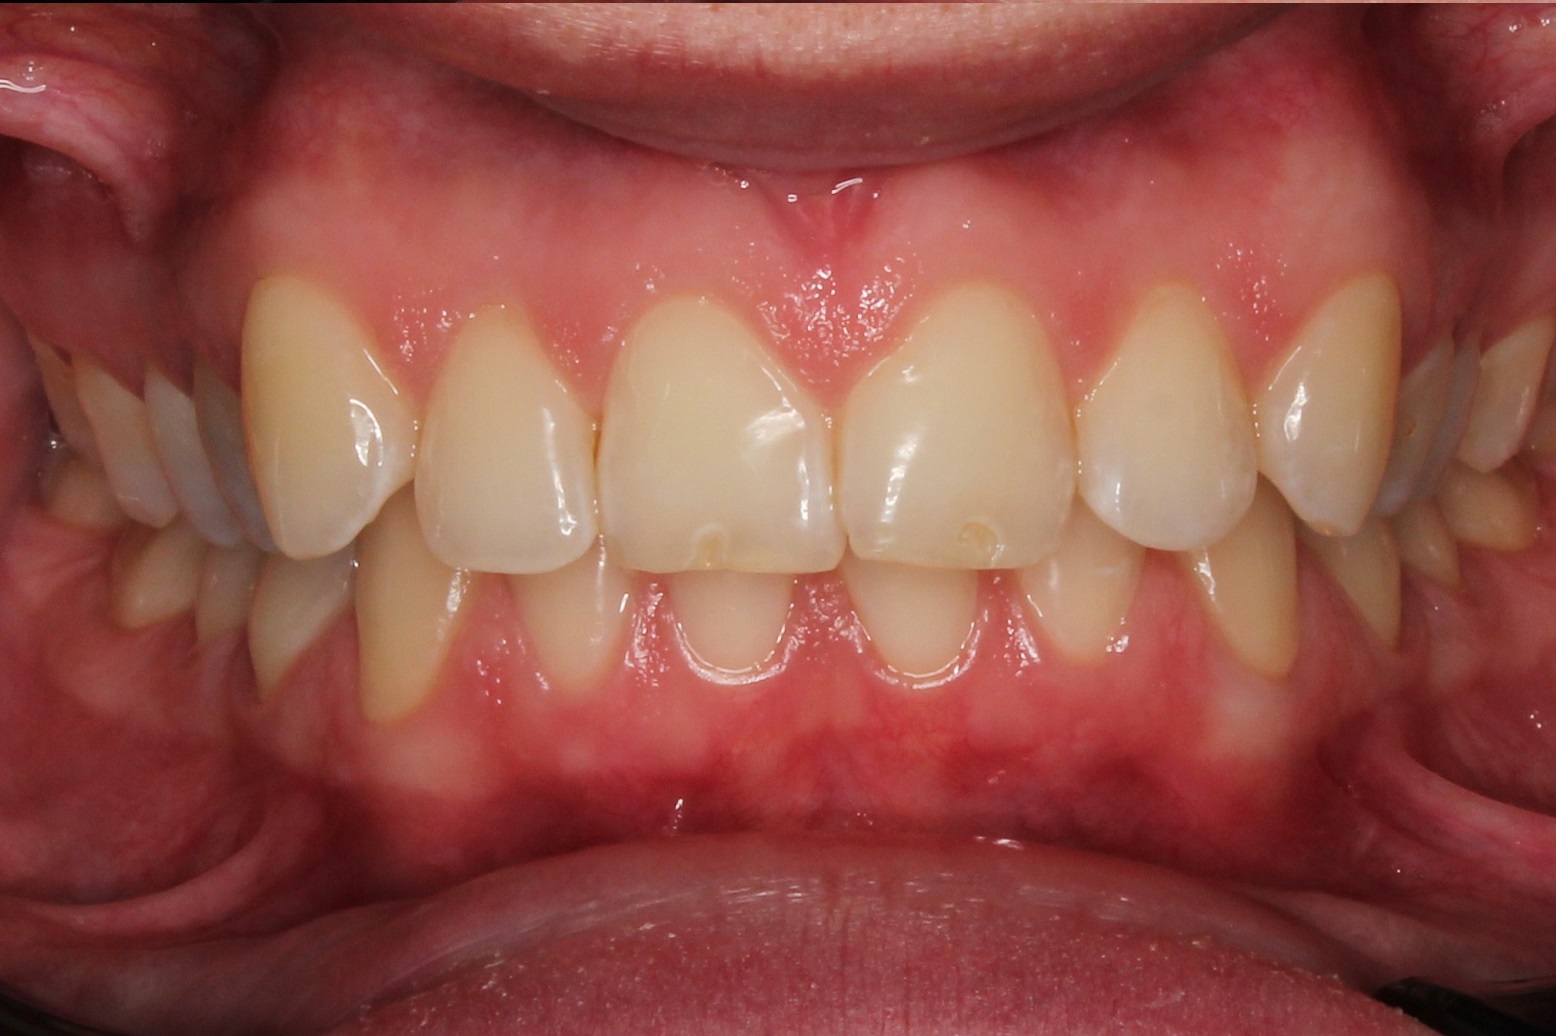

До и После: Лечение глубокого прикуса с помощью элайнеров Eurokappa